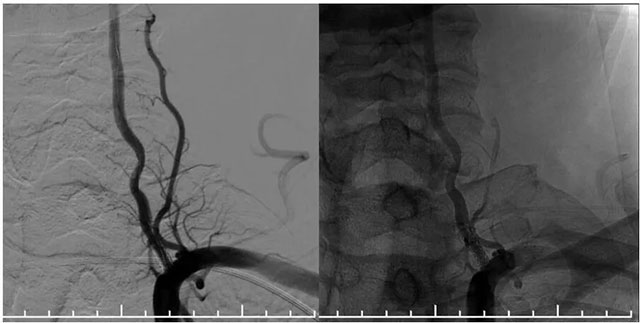

再次超選至左側(cè)鎖骨下動脈近椎動脈開口處,單次造影后明確開口狹窄程度,測量狹窄段長度及近遠端血管直徑,選取合適球囊。隨后在微導(dǎo)絲輔助下通過支架內(nèi)再狹窄段超選至左側(cè)椎動脈V2段,選用2.5*15球囊,沿微導(dǎo)絲到位于狹窄段,球囊擴張至8atm,再次行椎動脈造影,血流有所改善。再次將球囊下移,球囊擴張至14atm,撤除球囊后行即刻造影示血流較前通暢。選擇3.5*15藥物洗脫球囊,超選至狹窄處,予以6atm,后撤除球囊,行即刻造影示血流較前明顯改善,再次行椎動脈造影雙側(cè)大腦后動脈及基底動脈血流通暢。

▲ 藥物洗脫球囊在微導(dǎo)絲導(dǎo)引下到位于左側(cè)椎動脈支架內(nèi),充分?jǐn)U張藥物球囊使其貼壁

▲ 球囊擴張后,支架內(nèi)狹窄明顯改善,支架貼壁良好